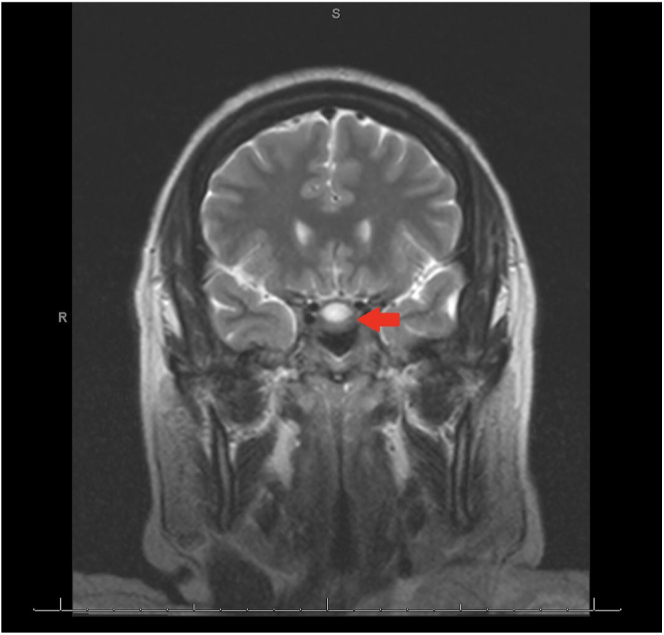

We report a case of a 43-year-old woman with stage IIB triple-negative breast cancer (TNBC) on neoadjuvant pembrolizumab presenting in adrenal crisis. Biochemical evaluation revealed isolated adrenocorticotropic hormone (ACTH) deficiency, and MRI demonstrated a partial empty sella; findings consistent with pembrolizumab-induced hypophysitis. Glucocorticoid replacement therapy led to symptom resolution. Pembrolizumab-induced hypophysitis is rare (incidence ∼0.98%), often associated with isolated ACTH deficiency, making diagnosis challenging due to nonspecific symptoms and frequently unremarkable pituitary imaging. As ICI use expands, clinician awareness of immune-related adverse effects (irAEs) is essential to prevent life-threatening complications and improve outcomes.

我们报告一例43岁女性IIB期三阴性乳腺癌(TNBC)新辅助派姆单抗呈现肾上腺危机。生化评估显示孤立的促肾上腺皮质激素(ACTH)缺乏,MRI显示部分空鞍;结果与派姆单抗诱导的垂体炎一致。糖皮质激素替代治疗导致症状缓解。pembrolizumab引起的垂体炎是罕见的(发生率约0.98%),通常与孤立的ACTH缺乏相关,由于非特异性症状和经常不显著的垂体成像,使得诊断具有挑战性。随着ICI使用的扩大,临床医生对免疫相关不良反应(irAEs)的认识对于预防危及生命的并发症和改善预后至关重要。